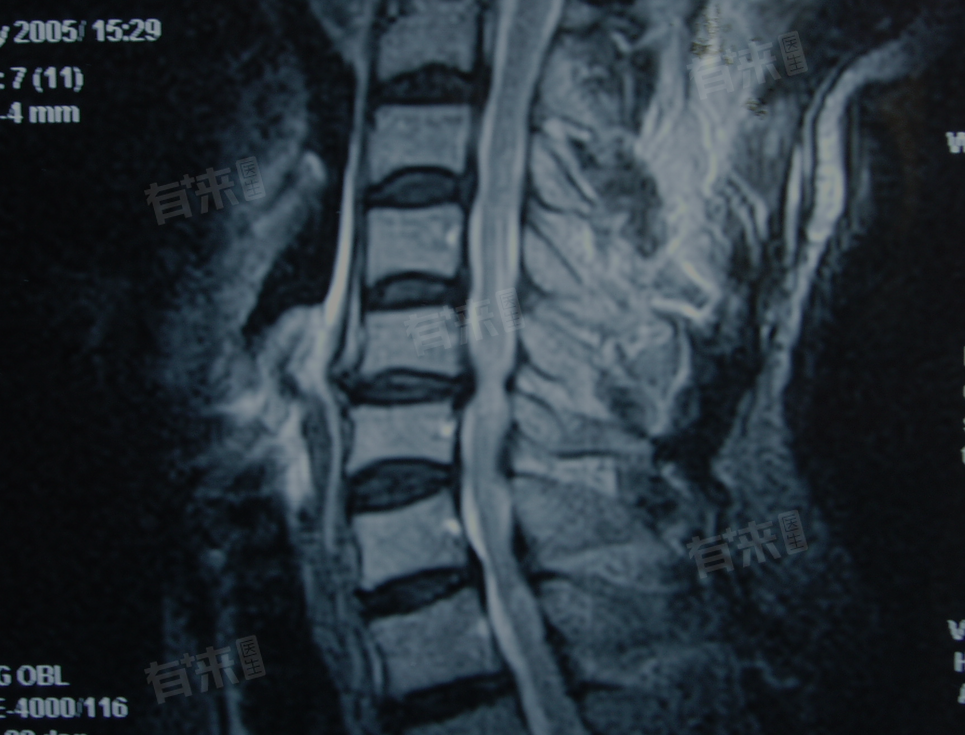

- 当硬膜囊受到异常外力作用或周围结构的侵入时,就会出现硬膜囊受压的情况。其中脊柱椎体的退变是常见原因之一,随着年龄增长,椎体间起缓冲作用的椎间盘会逐渐失去水分,变得愈发单薄,使得椎体相互靠近,周边的韧带等结构也可能随之增厚或膨出,进而对硬膜囊产生压迫。

- 此外,椎间盘突出也是导致硬膜囊受压的重要因素,椎间盘内部呈凝胶状的部分若突破外部纤维层向外突出,便会直接挤压硬膜囊。这种突出可能源于突然的外伤,如摔倒、重物搬运时的意外,也可能是长期不良姿势或脊柱反复受力,日积月累造成的结果。

- 硬膜囊受压带来的后果需要引起重视,由于硬膜囊内包裹着脊髓和神经根,一旦受压,神经信号的正常传递就会受到干扰。这通常会引发一系列症状,例如受影响神经根所支配区域会出现疼痛、麻木和刺痛感。若压迫发生在腰椎部位,就可能致使下肢出现疼痛和无力,因为支配下肢的神经根受到了影响。

在严重情况下,长期的硬膜囊受压甚至会导致更严重的神经功能缺损。脊髓作为中枢神经系统的关键部分,若压迫得不到缓解,极有可能受损。这可能引发肌肉协调障碍、大小便失禁,极端情况下甚至会导致瘫痪,此类患者可以前往医院骨科就诊,明确诊断后,在医生指导下进行针对性治疗。